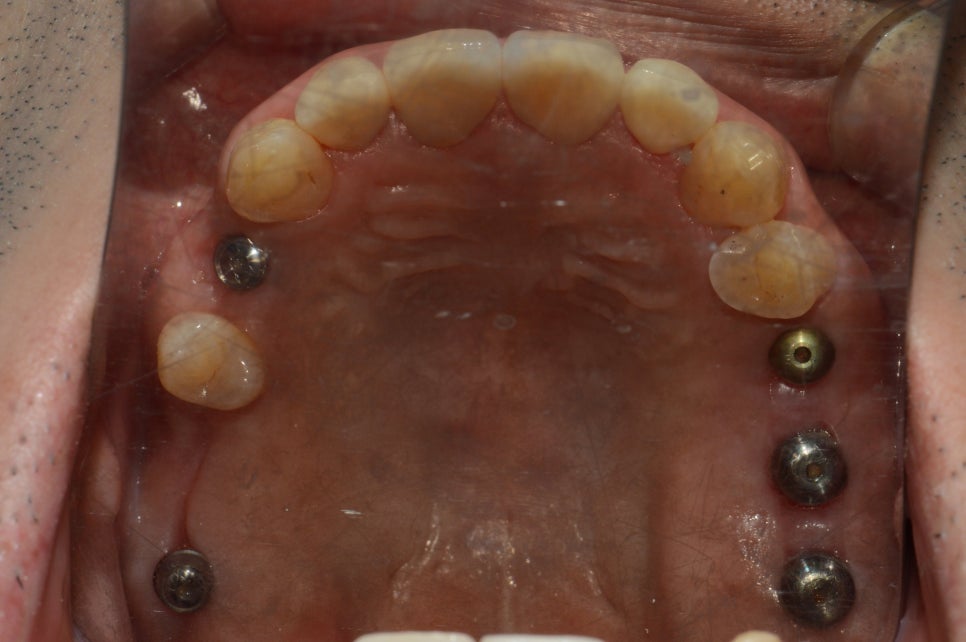

아름드리치과에서는

최소침습(무절개 무봉합) 임플란트로

통증없는 임플란트 치료가 가능합니다.

치료가 완료된 상태입니다.

환자분께서 힘든 시간을

잘 따라와 주셔서 만족스러운 결과가 나올 수 있었습니다.